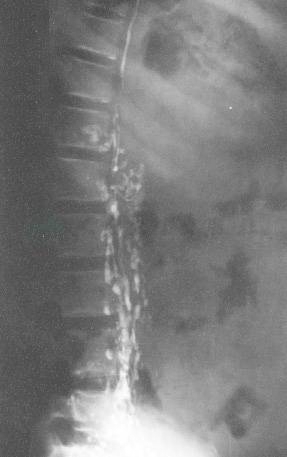

图7直接淋巴管造影显示胸导管颈段发育不全、狭窄

图8直接淋巴管造影显示胸导管呈多干,末端梗阻,碘油向右胸导管、纵隔及支气管淋巴干反流